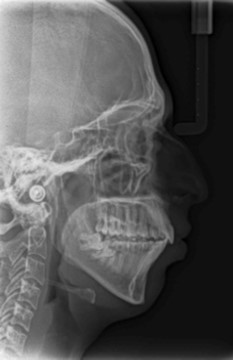

Cephalometric analysis revealed a skeletal Class II pattern, with an orthognathic maxilla and retrognathic mandible with high mandibular plane angle and severely proclined maxillary and mandibular incisors with increased lower anterior facial height. (Figure 3).

Post treatment lateral cephalometric radiograph was taken to assess the treatment changes. (Figure 9). The changes in maxilla in the anteroposterior direction was insignificant, however an increase in the length of the mandible measured from Condylion (Co) to Gnathion (Gn) and an increase in anterior facial height was observed. Maxillary incisors were retracted dramatically by 8mm and the mandibular incisors were proclined by 3mm to camouflage the skeletal class II malocclusion.(Table 1). Effective expansion of the maxillary constriction as an end-of treatment goal was achieved. (Figure 10a,Figure 10b).